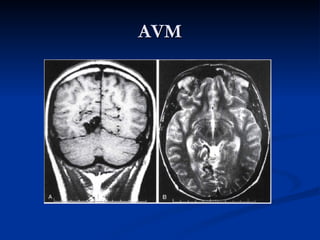

AVM

   Abnormalities of the intracranial vessels that

constitute a connection between the arterial and

venous systems and that lack an intervening

capillary bed.

Nidus , art.Feeder & venous drainage

   High flow , low pressure

   Arterialization of veins

   Smooth muscle proliferation

   Gliotic nonfunctional brain

   Perilesional ischemia

   Wegde shape lesion

AVM imaging